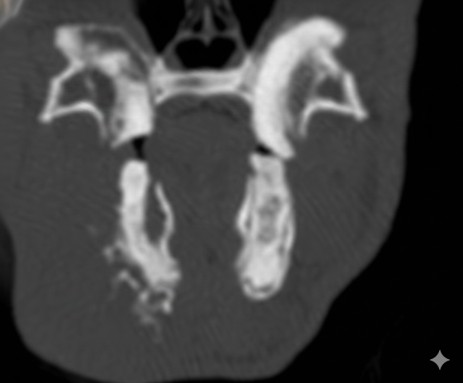

正確に診断するにはCT検査が必要になります。ウサギは無麻酔で撮影が可能です。

歯根はX線検査をで評価をしますが、左右、上下が重なっての評価になり、全ての異常を確認することはできません。

基本的には切歯を肉眼で観察し、口の中に耳鏡などを入れて臼歯を観察します。ただし目視で観察できるのは歯肉から出ている歯冠のみで歯根は見れません。